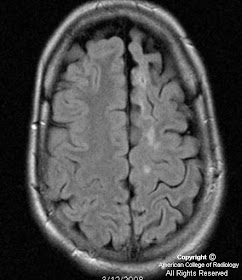

Figure 5: Unihemispheric volume loss involving the left hemisphere.

On imaging, Rasmussen encephalitis appears as unilateral cortical atrophy on CT and MR. There may be cortical swelling initially, with atrophy that ensues. The distribution is variable, although in some cases the entire cerebral hemisphere may be affected. No enhancement is usually seen. On PET/SPECT, there is decreased cerebral perfusion and hypometabolism of the affected hemisphere. There may be crossed cerebellar diaschisis although this is nonspecific. EEG is recommended to characterize the seizures.